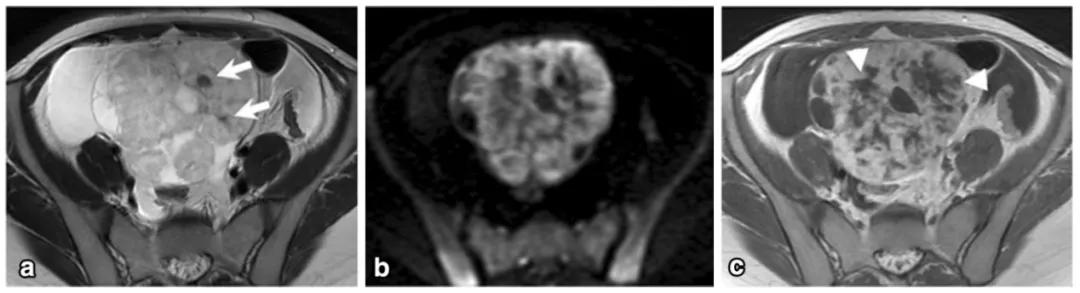

女,61 岁,雌激素升高。MR 显示左卵巢实性肿物,T2WI 呈稍高信号(图 a),内部多发小囊变(白箭),DWI 呈高信号(图 b),增强扫描明显强化。T2WI 显示子宫腺肌症(箭头)。